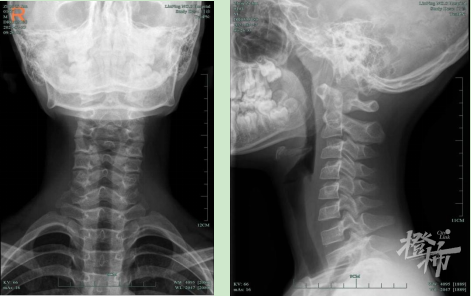

医生通过颈部触诊、问诊综合分析,初步判断小杰为颈椎问题。颈部DR片检查结果显示,小杰颈椎病变严重,竟然超过许多成年人的情况。

小杰的颈部DR检查结果